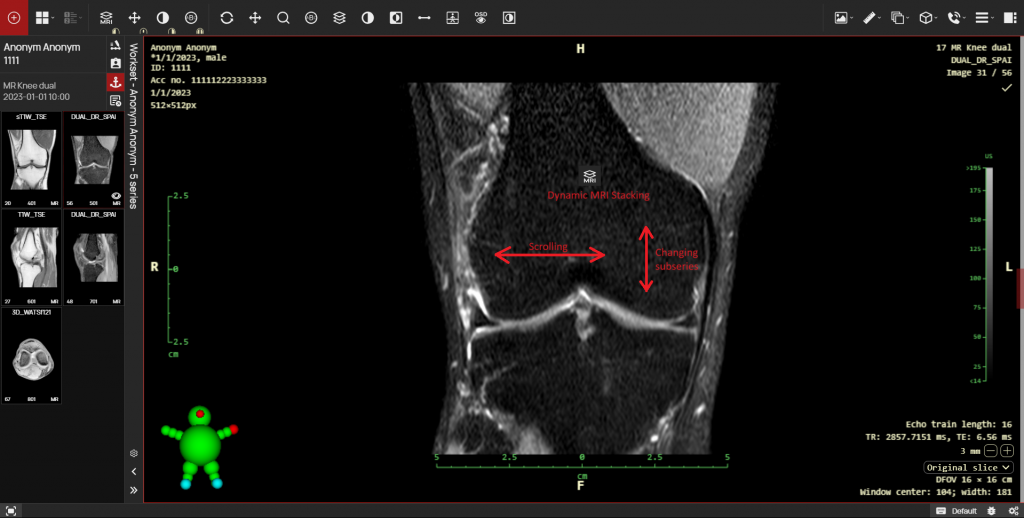

- Lower limb angle measurements have been modified in this version of the DICOM viewer and now also show laterality angles. The laterality of the angles can be determined using the right sidebar in the “Measurement toolset”, drop-down menu ‘Laterality’ in the “Lower limb angles” tab. After measuring the lower limb angles, the following angles are displayed:

- HKA – hip-knee-ankle angle

- mLDFA – mechanical lateral distal femoral angle

- mPTA – medial proximal tibial angle

- JLCA – joint line convergence angle